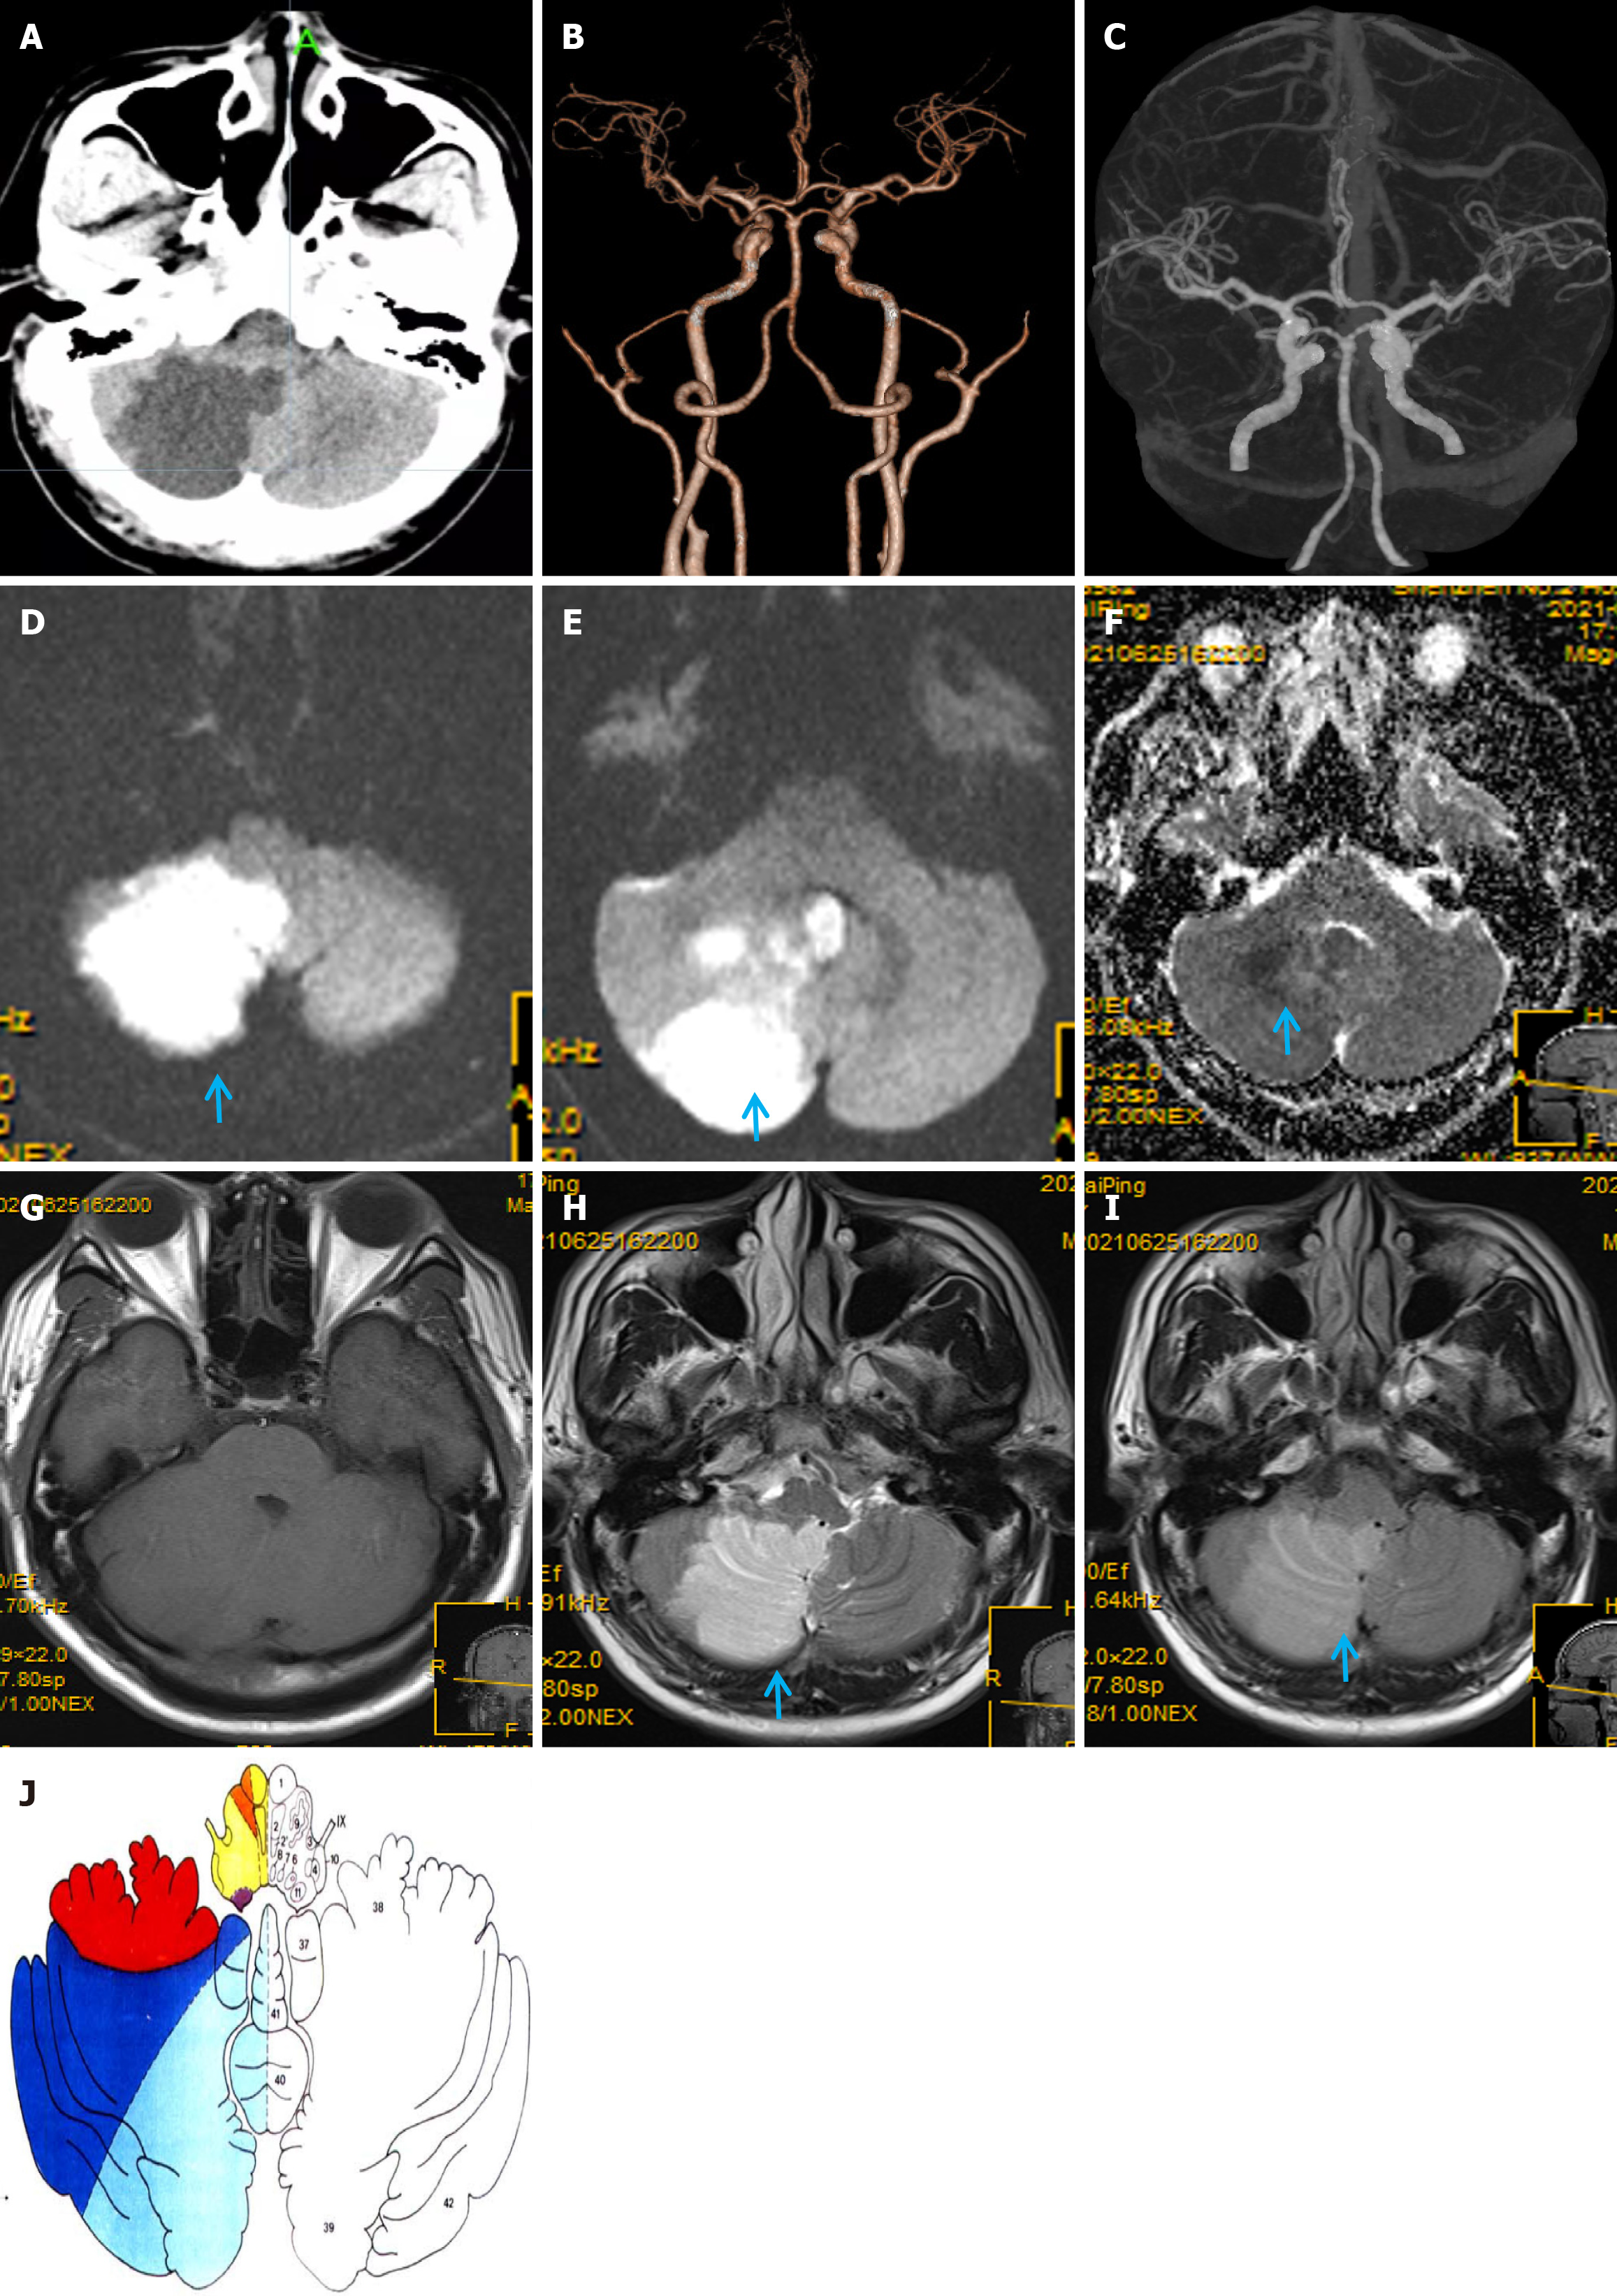

Massive right cerebellar infarction was observed on the head computed tomography (CT; Figure 1A) with no obvious abnormalities on craniocervical CT angiography (CTA; Figure 1B and C).

Chest CT showed scattered exudative lesions in both lungs, and bilateral lower lobes were clearly visible. Abdominal CT showed mild fatty liver, and echocardiography, contrast transcranial Doppler, contrast echocardiography, and 24-hour dynamic electrocardiography revealed obvious abnormalities. Furthermore, 1.5-T magnetic resonance imaging (MRI) showed a massive acute right cerebellar infarction (Figure 1D-I) in the area supplied by the PICA (Figure 1J)[7], with no obvious abnormalities on gadolinium-contrast magnetic resonance angiography (MRA) (Figure 2A). Moreover, 3.0-T high-resolution vessel wall (HR-VW) MRI showed right PICAD (Figure 2B-D).

Diagnosing PICAD is often difficult and requires close and repeated imaging evaluations. Here, PICAD was identified by its characteristic origin from the distal vertebral artery (VA) and its unique trajectory around the medulla oblongata, to supply the inferior cerebellum (Figure 1J). In contrast, the VA primarily supplies the medulla oblongata, pons, and dorsal portions of the cerebellum. On HR-VW MRI, the PICA can be distinguished by its smaller caliber and distinct course compared with the larger VA. Therefore, differentiation is primarily based on the anatomical relationships, blood supply regions, and specific imaging features. PICAD should be considered a differential diagnosis in patients with of PICA territory infarction (Figure 2).